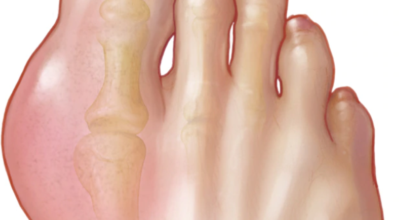

엄지발가락 통증 - 무지외반증

우리에게 잘 알려져 있는 엄지발가락 통증의 원입니다. 선천적 요인으로 인한 발병보다는 하이힐, 뾰족구두, 키높이 깔창과 같이 앞이 좁고 엄지발가락에 자극이 심한 신발 유행으로 후천성 환자가 늘어나고 있는 모습입니다. 체중 증가나 류마티스 관절염도 무지외반증의 이유가 되는 것입니다. 엄지발가락이 둘째 발가락으로 휘어지면서 대측으로 회전해서 제1중족 관절이 안쪽으로 돌출되는 무지외반증은 서있거나 걸어 다닐때 신발과 마찰해 통증과 염증이 발생해요.